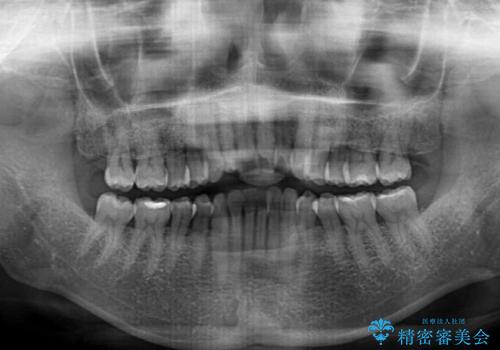

- 前歯の上下スペースによる食べにくさを気にして来院された患者様です。

インビザラインにより上下の前歯の隙間を閉じていくこととしました。

舌の突出癖があると上下前歯にスペースが開くため、矯正治療を機会に舌癖を改善するトレーニングを行ってもらい、矯正治療後の後戻りを防止するように指導しています。